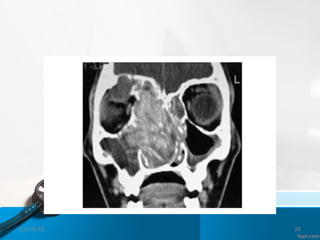

CT Scan

01/19/16 26

01/19/16 27

Maxillary sinusitis